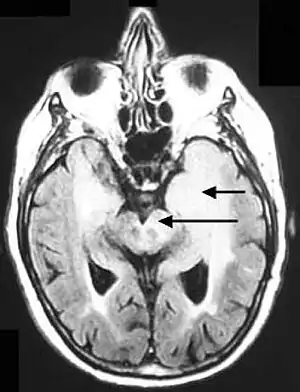

| Axial fluid-attenuated inversion recovery MRI image demonstrating tumor-related infiltration involving both temporal lobes (Short arrow), and the substantia nigra (Long arrow). | |

Before the advent of MRI, diagnosis was generally not established until autopsy. Even with MRI, however, diagnosis is difficult.[3] Typically, gliomatosis cerebri appears as a diffuse, poorly circumscribed, infiltrating non-enhancing lesion that is hyperintense on T2-weighted images and expands the cerebral white matter. It is difficult to distinguish from highly infiltrative anaplastic astrocytoma or GBM.